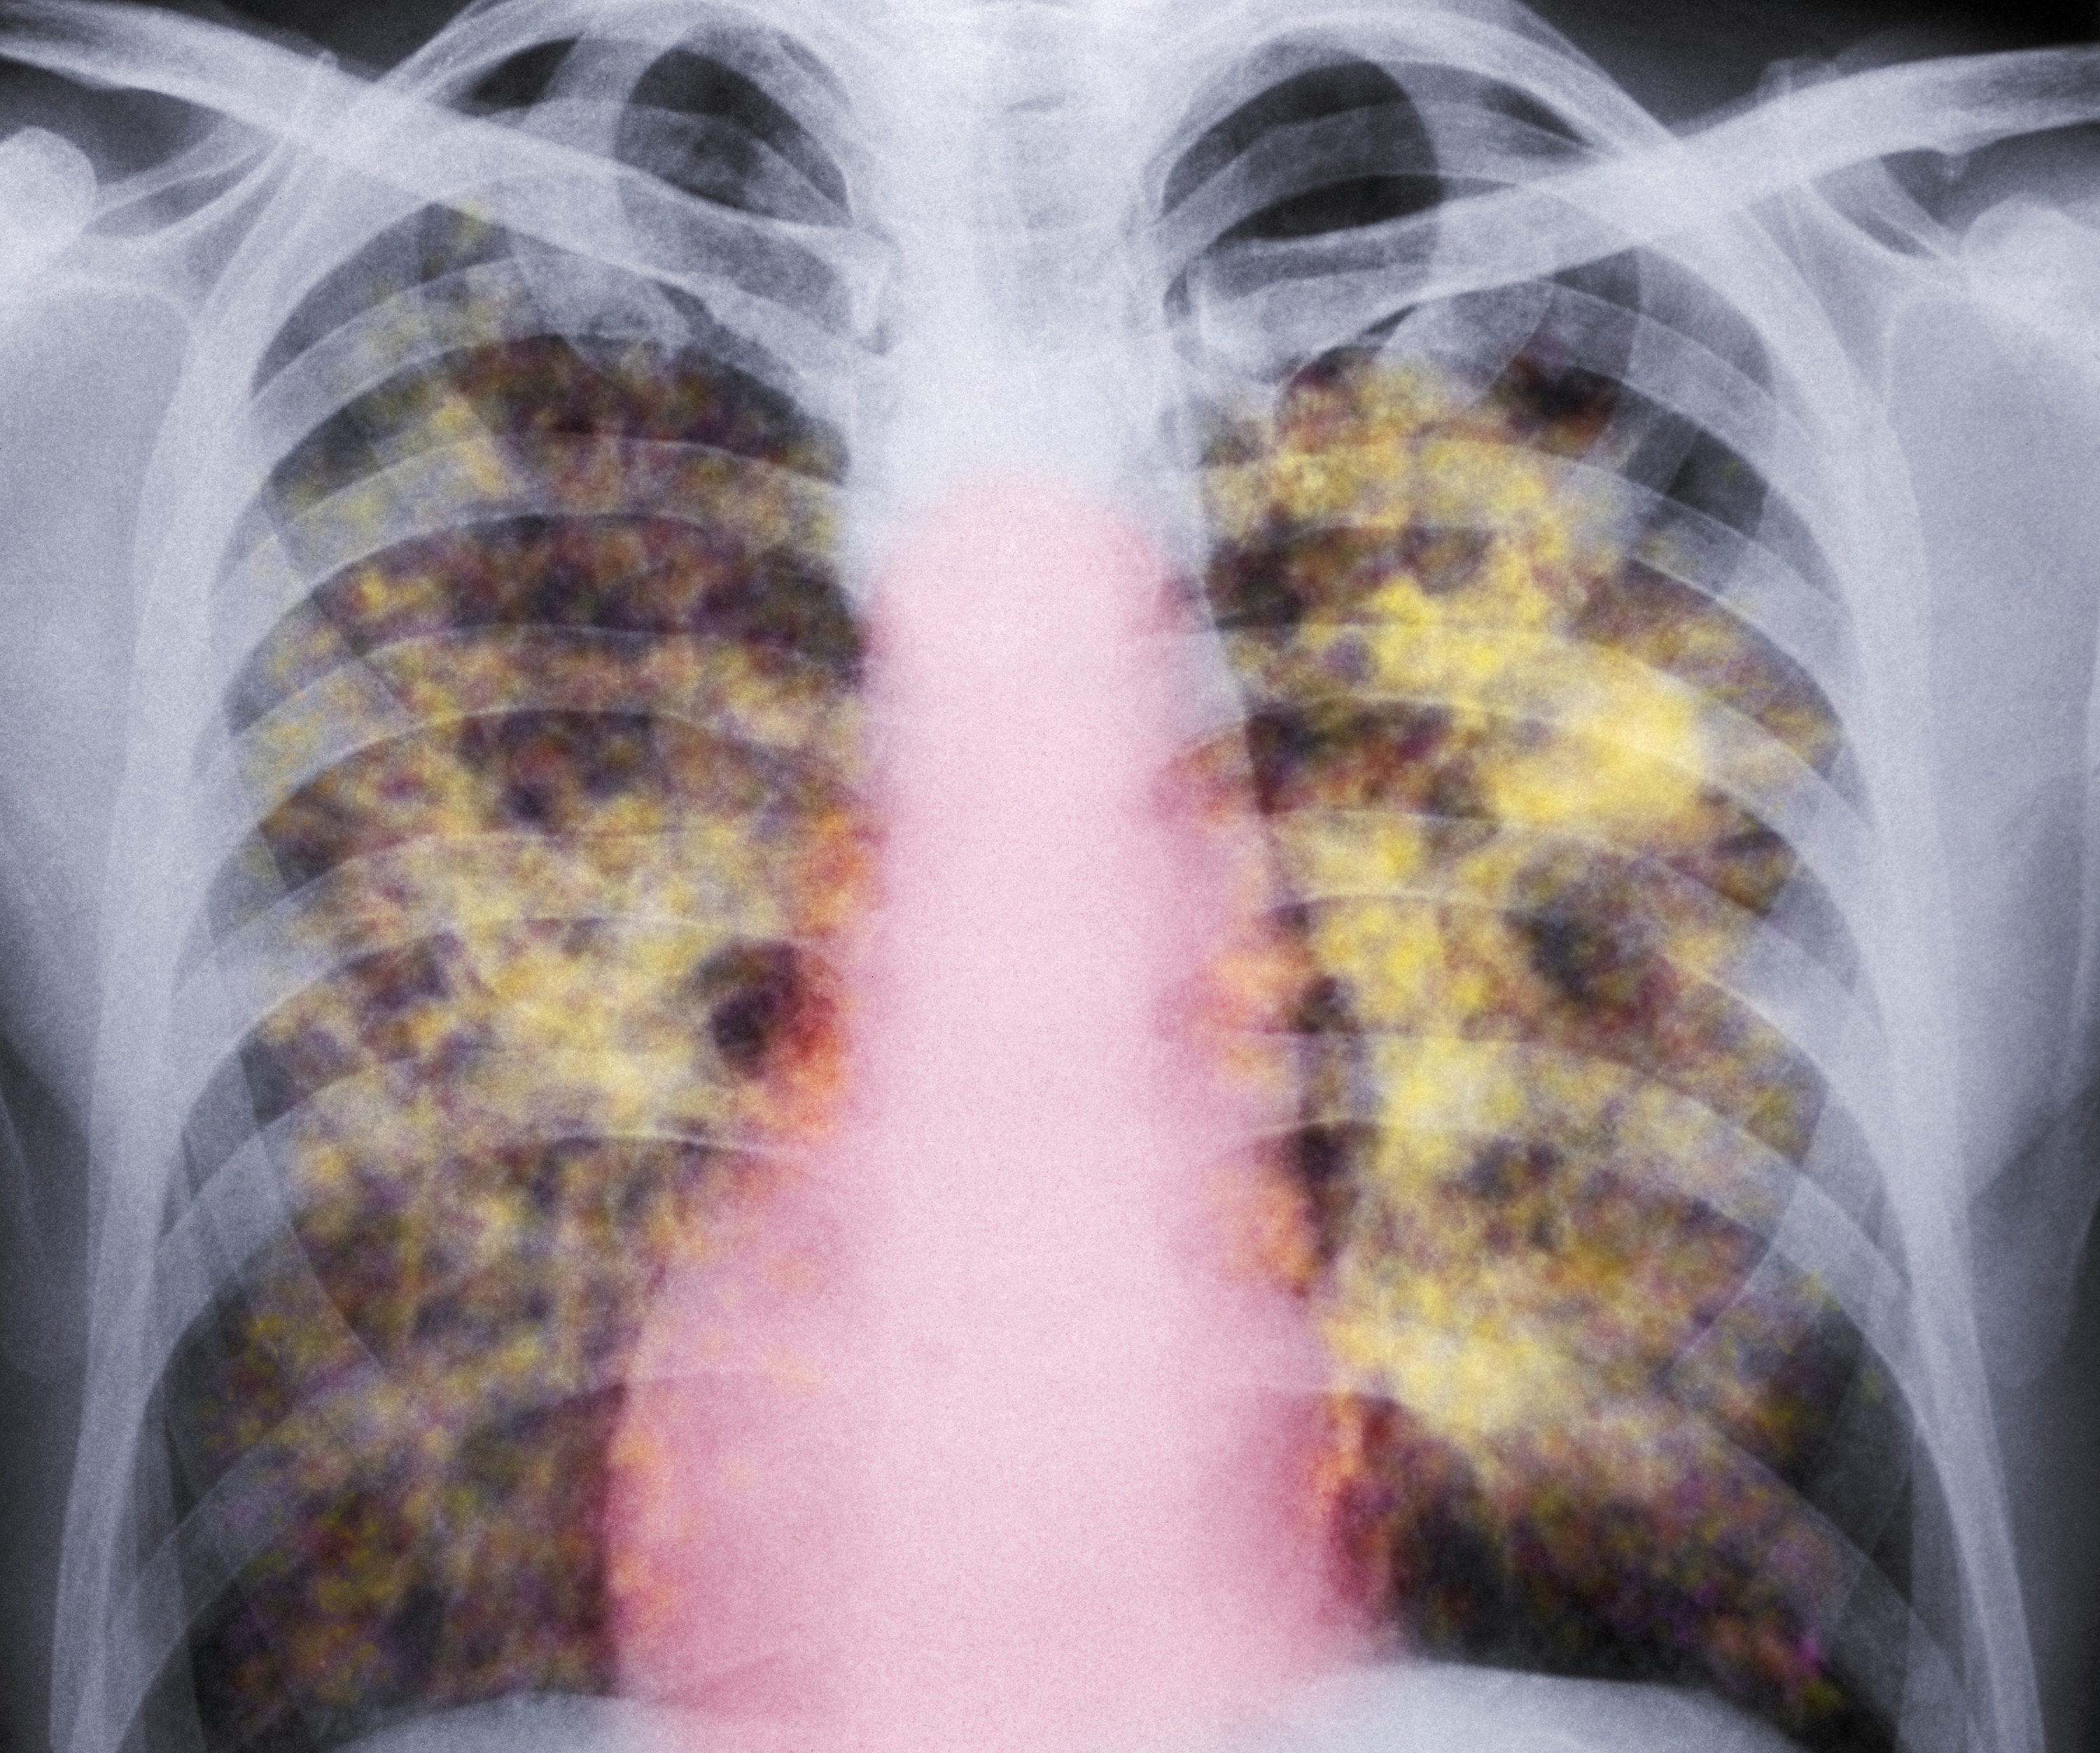

A colored X-ray of the lungs of a patient with silicosis, a type of pneumoconiosis. The yellow grainy masses in the lungs are areas of scarred tissue and inflammation. (CNRI/Science Photo Library/Getty Images)